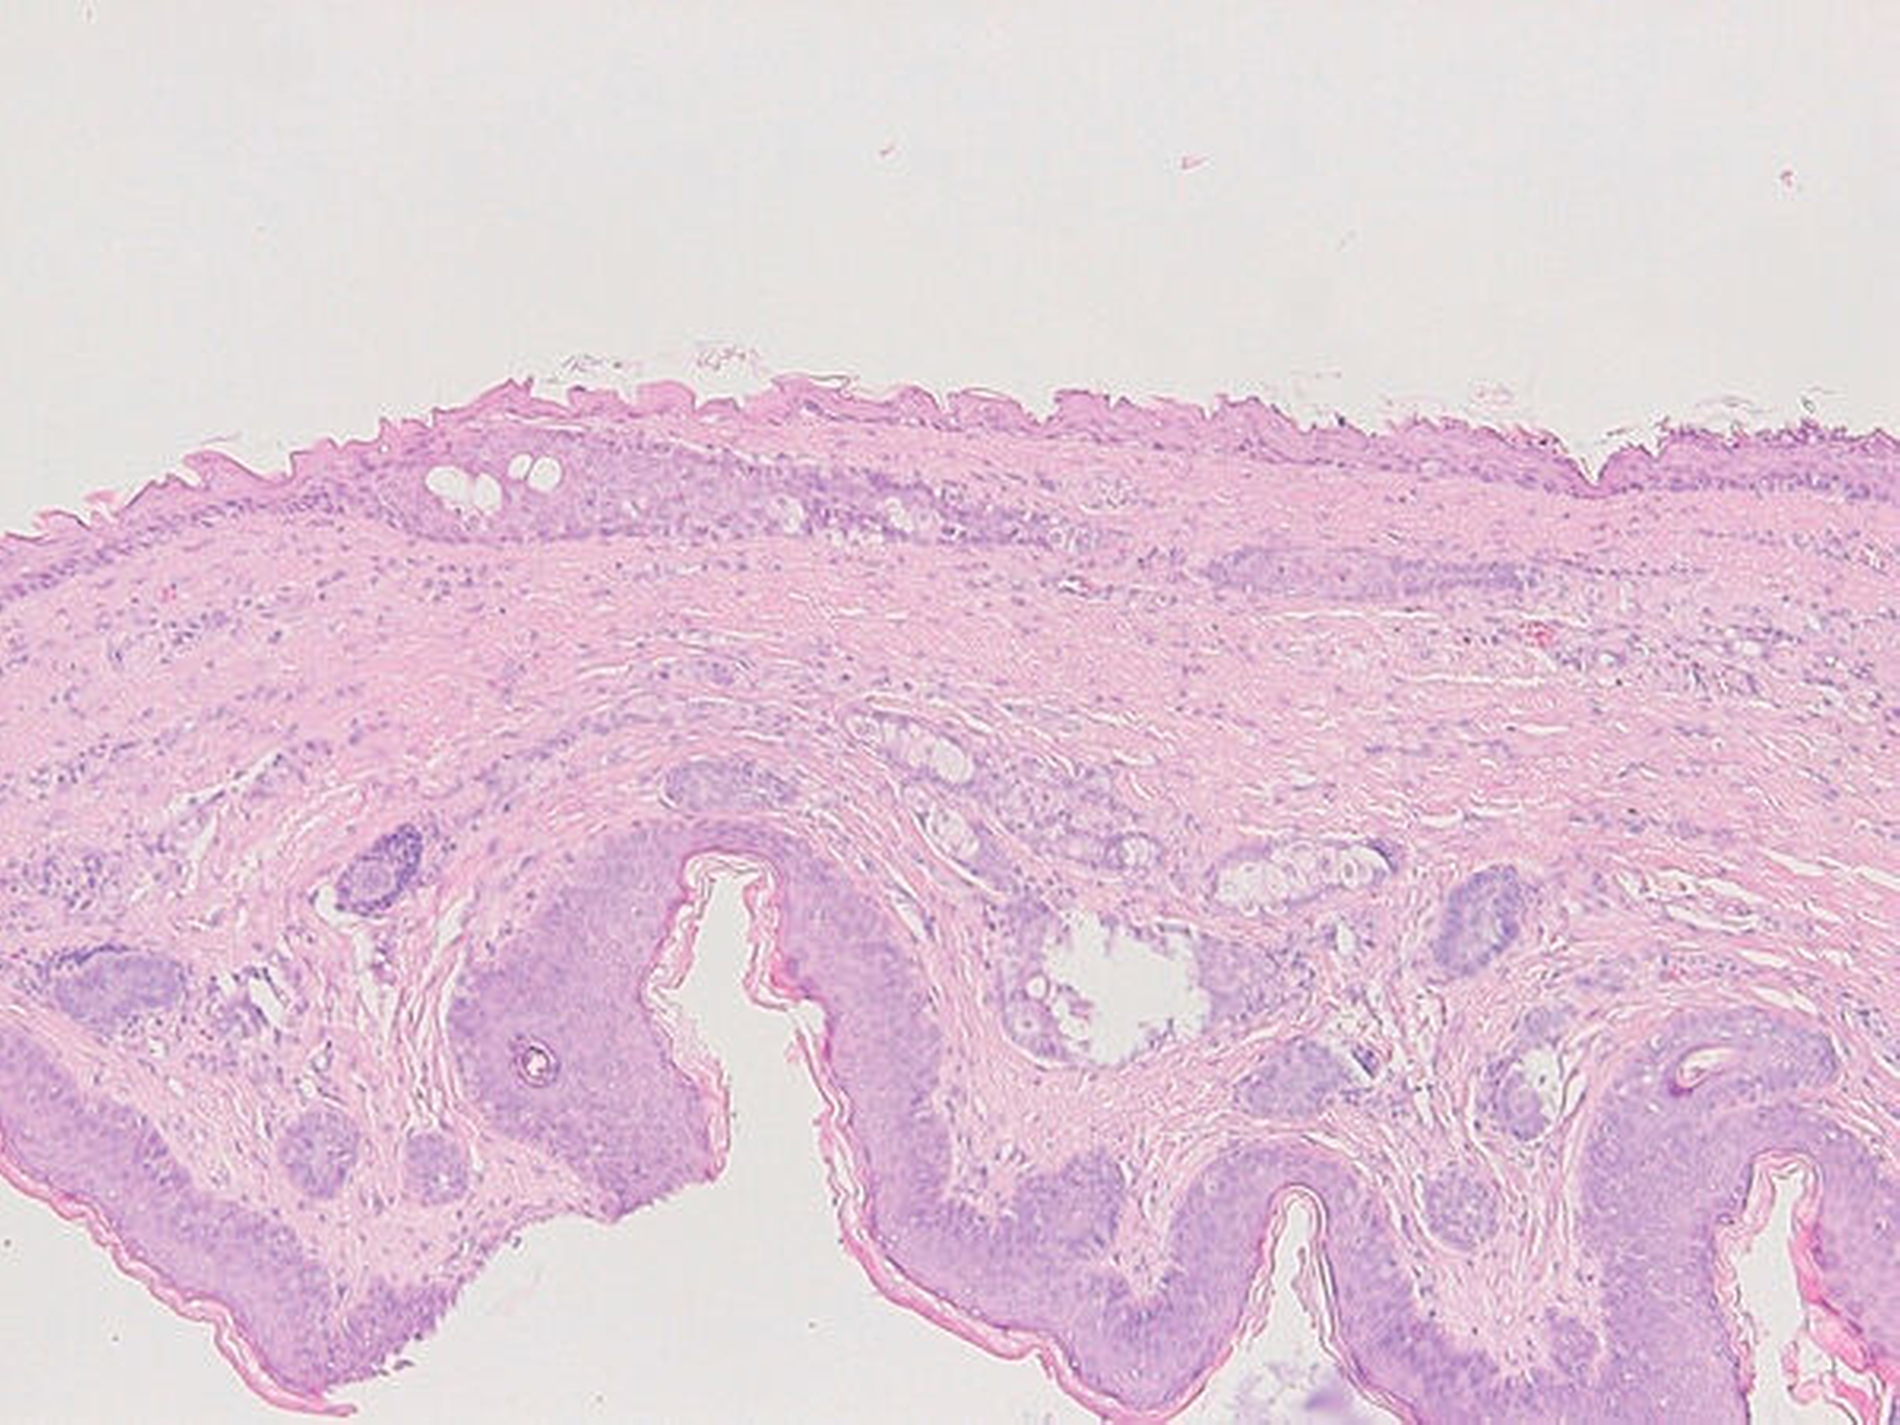

Zwei Wochen nach der Erstvorstellung erfolgte die komplikationslose Resektion in Intubationsnarkose (Abbildung 4). Im histologischen Bild sieht man eine vollständig entfernte Dermoidzyste (Abbildung 5). Bei der Nahtentfernung in Sedierung eine Woche nach der operativen Intervention wurde zeitgleich zum sicheren Ausschluss einer Meningomucozele und weiterer Pathologien eine Magnetresonanztomografie durchgeführt. Hierbei waren keine Residuen der Dermoidzyste sowie keine Fistelung nach intrakraniell auffällig. In den klinischen Nachkontrollen zeigten sich regelhafte und reizlose Wundverhältnisse (Abbildung 6).